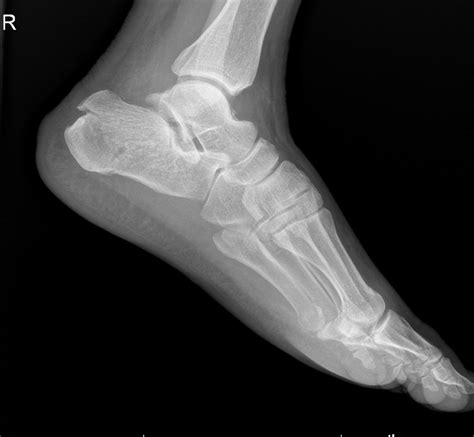

Diagnosing a Stress Fracture Heel

Accurate diagnosis is essential for effective treatment. A healthcare professional will typically perform the following steps to diagnose a stress fracture heel:

• Imaging Tests: X-rays, MRI, or bone scans may be ordered to visualize the fracture and rule out other conditions.